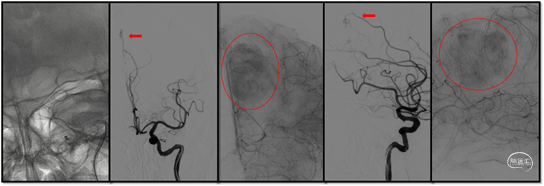

图3:脑血管造影可见肿瘤供血动脉主要为①左侧大脑前动脉的分支胼缘动脉(白箭);②右侧脑膜中动脉(红箭)

图4:左侧颈外动脉、右侧颈内动脉及椎动脉未见向肿瘤供血。

(3)此时中间导管相对稳定,保留颈内动脉内的V-18导丝在导管内支撑,用PT导丝携带微导管置于左侧颈内动脉床突段,在微导丝及微导管导引下进一步将中间导管头端通过颈内动脉岩骨段膝部置于水平段。此时V-18导丝内衬在中间导管内进行支撑。中间导管到位后行正侧位造影,可见左侧胼缘动脉向肿瘤供血,毛细血管期可清晰见到肿瘤轮廓浓染,提示肿瘤血供极其丰富。

(5)用DMSO 0.27ml冲洗Marathon微导管,将预混匀的Onyx-18胶缓慢注入约2ml。可见Onyx胶弥散至瘤内各处,尤其在早期弥散至对侧向前的血管考虑可能为右侧脑膜中动脉向瘤内供血通路(红箭)。

(6)左侧颈内动脉造影肿瘤染色基本消失,右侧颈总动脉造影发现右侧脑膜中动脉向瘤内供血也已消失,再次经左侧颈总动脉造影可见肿瘤染色基本消失,已达到供血动脉栓塞目的,撤出导管导丝结束手术。